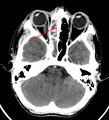

Left-sided maxillary sinusitis marked by an arrow. Note the lack of the air transparency indicating fluid in contrast to the other side.